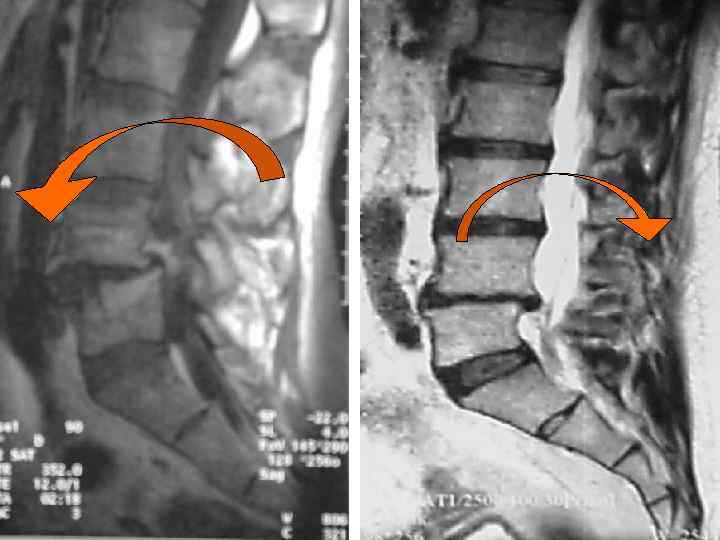

Спондилолиз Спондилолистез

Спондилолистез